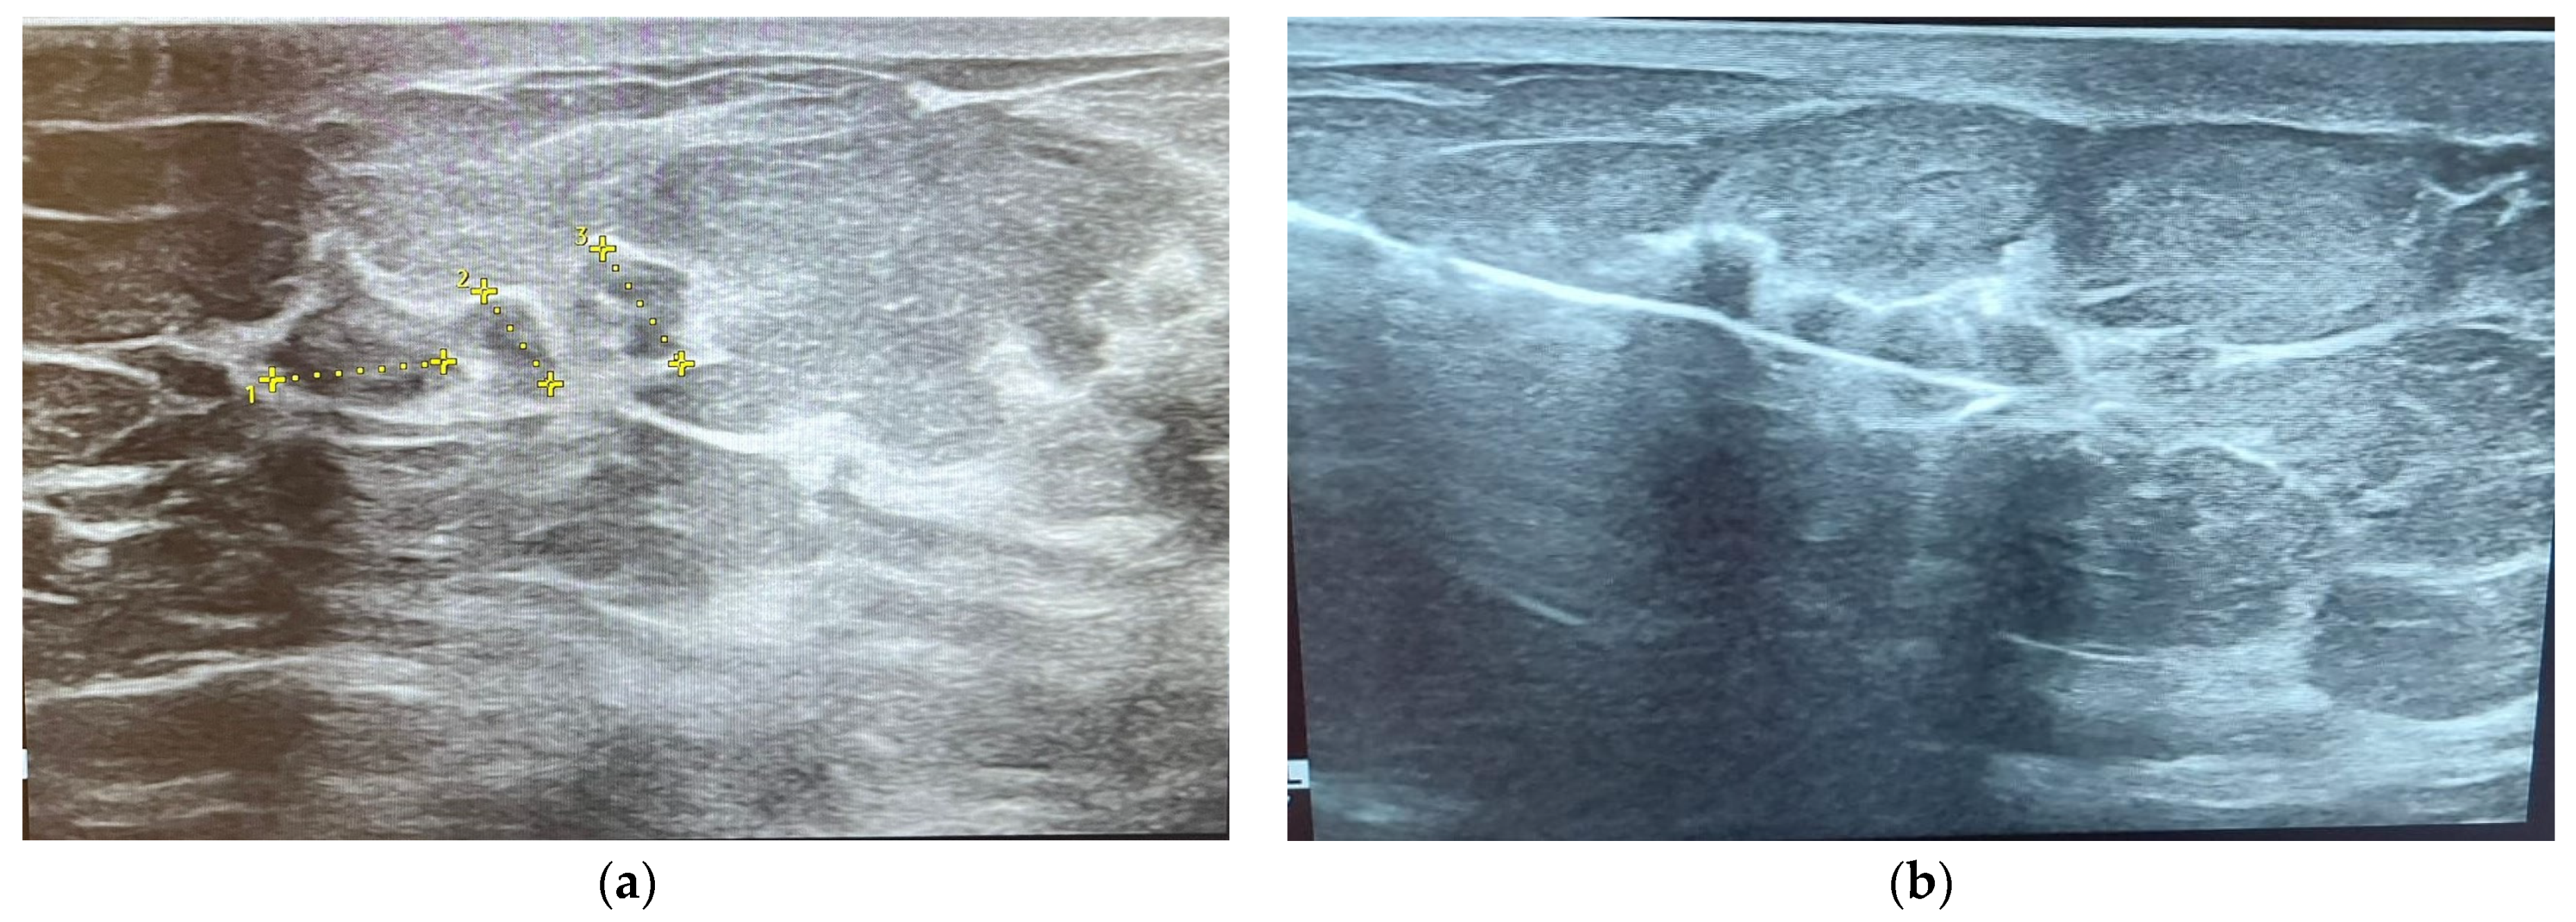

2.3. Ultrasonography (US)